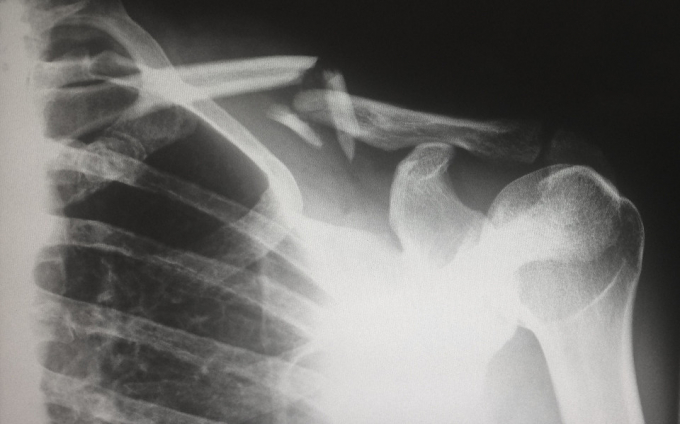

2. Перелом

Симптоми:

- Сильний біль у кістках.

- Чутливість.

- Набряк.

- Синці на шкірі.

- Деформація кістки.

- Неможливість поворухнути кінцівкою.

Більшість переломів спричинені сильними травмами, такими як нещасний випадок чи падіння. Збільшити їх ризик можуть такі захворювання, як остеопороз, рак та артрит.

Лікування залежить від типу перелому. При відносно простих переломах, що відбуваються під шкірою, використовується шина або гіпсова пов'язка, щоб знерухомити кістку і допомогти їй правильно зростатися.

У разі відкритих переломів або усунення може знадобитися хірургічне втручання. Іноді воно також рекомендується, якщо кістка не зростається належним чином.